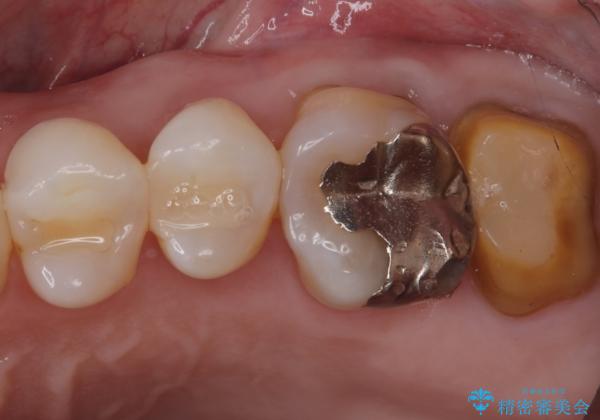

保険適応のメタルインレーと歯質との間に不適合な箇所を認め、補綴物のやり替えでの治療となりました。インレーからクラウンへ補綴物の形態を変更し、素材は清掃性・適合性・審美性の点からセラミッククラウンでのやり替となりました。

健全歯質の残存量から、クラウンでのやり替えを提案しオールセラミッククラウン(スタンダード)でのやり替えとなりました。

・オールセラミッククラウン(スタンダード) 121,000円(税込み)

・仮歯 11,000円(税込み)